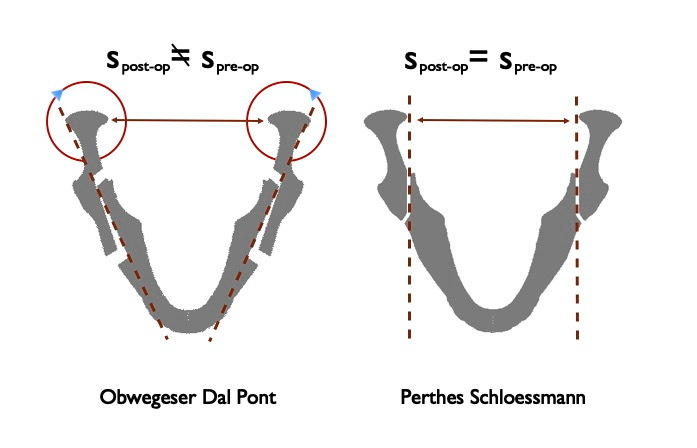

- Les angles mandibulaires sont moins déplacés dans la largeur, il y a donc moins d’élargissement des angles, et moins de répercussions sur les ATM.

Comparaison des effets sur les angles dans les deux techniques, dans le sens transversal.

Sur le schémas de gauche, avec la technique classique, les angles son écartés.

Sur le Schémas de droite, avec la technique haute, les articulations sont moins modifiées.